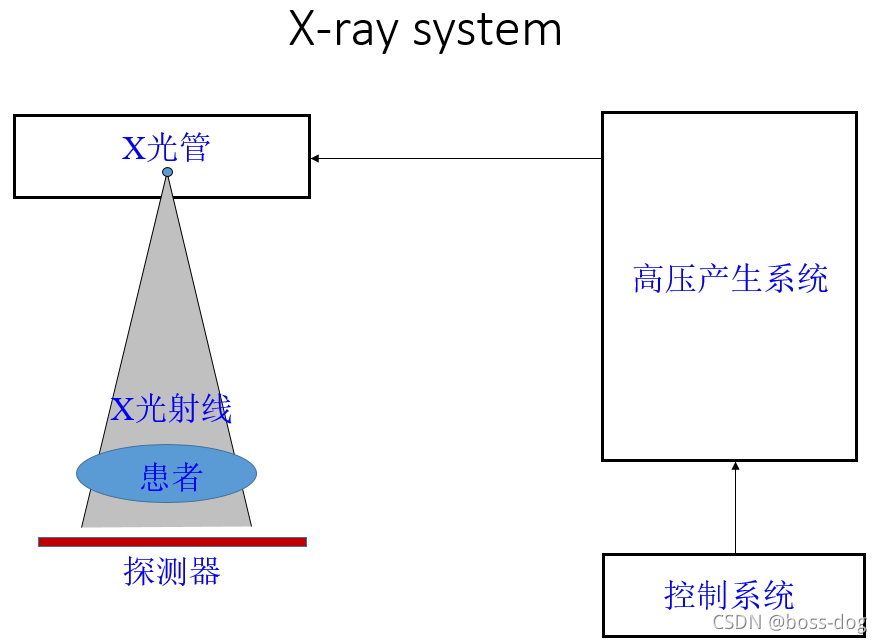

8.X光产生

X线检查技术与应用

高压产生系统作用:将220V交流电生成几千几万伏的直流高压,然后连接到X光管,通过X光管来产生X光,之后用X光来照射病人,最后做成像。